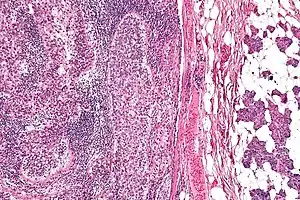

| Micrograph of a sebaceous carcinoma (left of image) metastatic to the parotid gland (right of image). H&E stain. | |